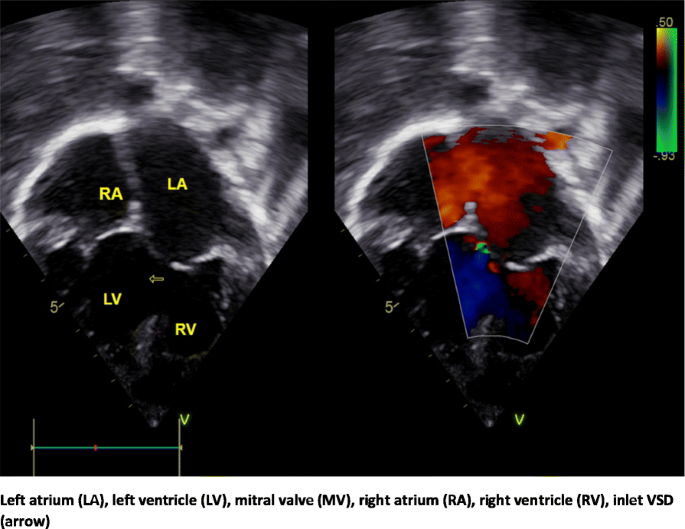

TTE showed ccTGA with mild mitral valve regurgitation through a cleft in the anterior leaflet. There was no tricuspid valve regurgitation. However, the septal leaflet of the tricuspid valve was seen straddling the interventricular septum and attaching to the septal surface of the morphological left ventricle (Fig. 2). There was a large inlet VSD of 26 mm in diameter (Fig. 3). The pulmonary valve was bicuspid with mild pulmonary valve stenosis. The ECG showed: normal P and QRS axis, the P rate was 100 bpm. There was complete atrioventricular dissociation with an ideo-junctional escape rhythm. The ventricular rate was 73 bpm. There were QR waves in lead V1 and RS in leads V5 and V6 (ECG Figure 2).